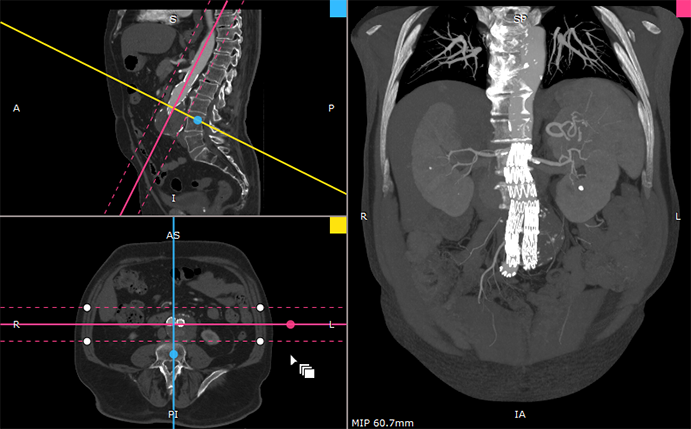

RadiAnt DICOM Viewer BETA 3.9.15 - further improvements in 3D MPR/MIP viewer - radiantviewer.com/thread.php?id_…

radiantviewer's tweet image. RadiAnt DICOM Viewer BETA 3.9.15 - further improvements in 3D MPR/MIP viewer - radiantviewer.com/thread.php?id_…